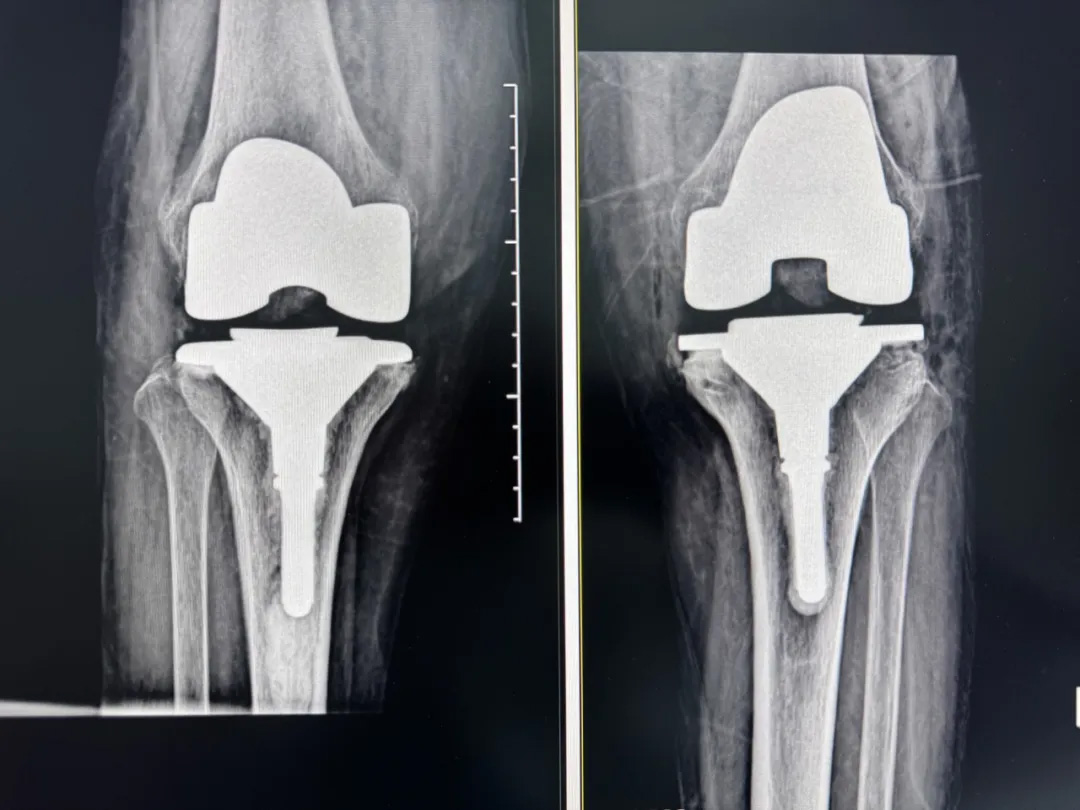

術(shù)前:AI通過CT掃描生成毫米級膝關(guān)節(jié)三維模型,為假體安裝設(shè)計出誤差小于1毫米的精準(zhǔn)方案 術(shù)中:智能導(dǎo)航系統(tǒng)如同"透視眼",引導(dǎo)醫(yī)生避開密集的神經(jīng)血管網(wǎng),截骨更精準(zhǔn),出血僅100ml 術(shù)后:當(dāng)天鄭阿婆即開始抬腿的康復(fù)訓(xùn)練,24小時內(nèi)扶助行器下地行走,三天后已能在病房走廊獨(dú)立行走,完成洗漱用餐 兩周后健步出院時,女兒含淚感慨“之前擔(dān)心她年紀(jì)大扛不住手術(shù),沒想到恢復(fù)這么快!現(xiàn)在每天散步比我還精神。知道技術(shù)這么先進(jìn),真該早點(diǎn)來!”

"這就像給傳統(tǒng)手術(shù)裝上了自動駕駛系統(tǒng)。"主刀醫(yī)生羅軍副院長用生動比喻解析技術(shù)突破。AI不僅實現(xiàn)假體“量身定制”,使用壽命可達(dá)20年以上,更通過三維路徑規(guī)劃將康復(fù)周期壓縮,實現(xiàn)術(shù)后24小時下地,2周回歸正常生活。同時,AI會避開重要組織,具有出血少、感染風(fēng)險低的特點(diǎn)。專家特別提醒,當(dāng)出現(xiàn)夜間持續(xù)性關(guān)節(jié)疼痛、步行能力低于10分鐘或關(guān)節(jié)畸形時,應(yīng)及時就醫(yī)評估,"別等到關(guān)節(jié)'報廢'才手術(shù)"。